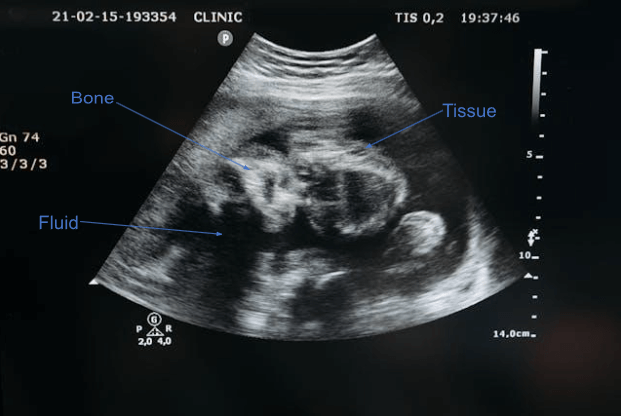

How to Read Your Sonogram at Monthly Checkups

A sonogram uses sound waves to create an image of your baby, which can look abstract at first glance.

(Image: Dr Sono)

Colour on Sonogram |

What They Represent |

Black |

Fluid |

Grey |

Soft tissue |

| Bright white |

Bones |

During each scan, your doctor checks key markers like the heartbeat, growth measurements, and overall structure. You may see lines and numbers on the screen, which help track your baby’s development over time. What matters most is steady growth and a healthy heartbeat, rather than the exact figures shown.

The scan also allows your doctor to assess movement, amniotic fluid, and placenta position.